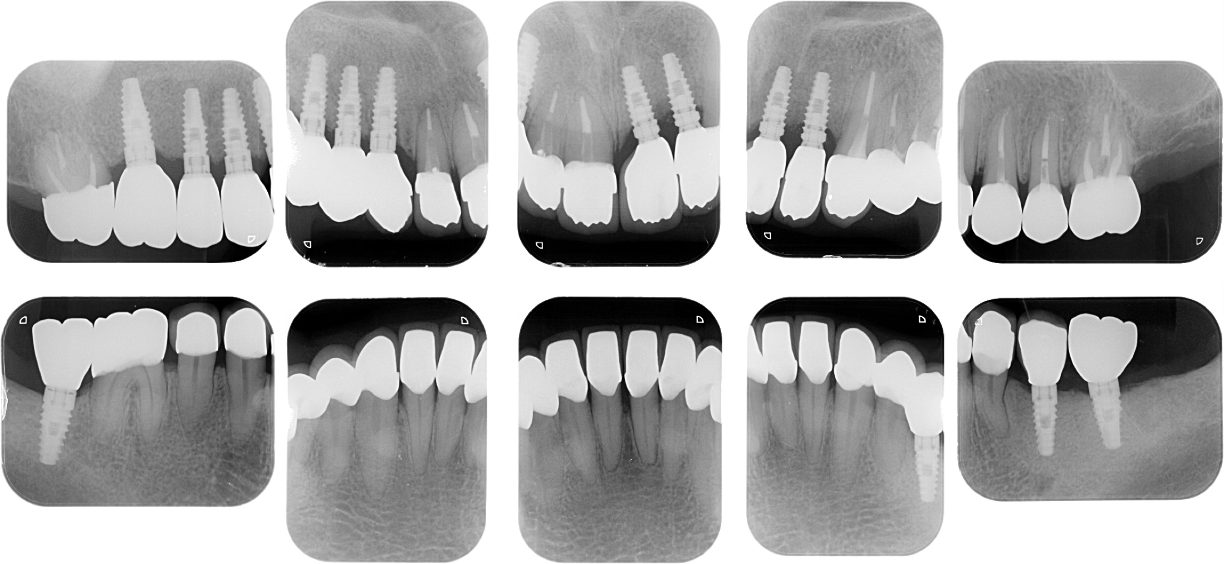

多数歯欠損のインプラント治療の症例(うえだ歯科)

| 主訴 | 歯がグラグラで噛むことができない。インプラントをして欲しい。 |

| 治療内容 | 歯周病で骨の吸収が重度で保存不能なため抜歯、仮の入れ歯を作り、6ヶ月の抜歯窩の治療の後に、インプラントのCTによる診査診断を行い、下顎に6本インプラント埋入と同時に仮歯を入れる。その後、上顎は8本のインプラント埋入と同時に仮歯を入れる。左右上6はソケットリフトによる上顎洞拳上術を行う。その後免荷期間6ヶ月待ってセラミックを用いた上部構造作製、装着しメンテナンスに移行する。 |

| 治療費 | 9,000,000円(税込) |

| 治療期間 | 2年3ヶ月 |

| 治療回数 | 90回 |

| 想定されたリスク | 重度の歯周病により無歯顎になったため、プラークコントロール不良による、術後のインプラント周囲炎が懸念される。歯冠の部分はセラミックなため欠ける可能性がある。 |